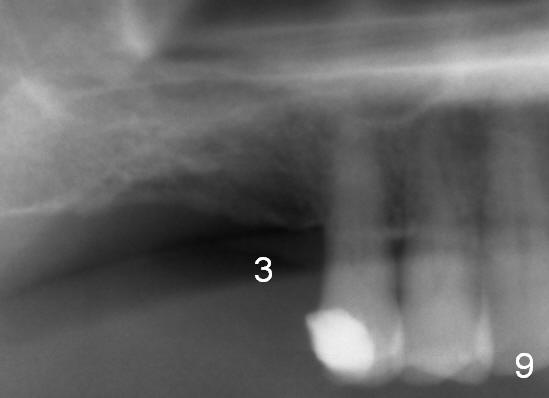

When the patient returns for impression 6.5 months postop, the provisional has dislodged because of the short abutment (Fig.7 A (6.5x4(2) mm). A longer one is placed (6.5x5(3) mm). When he returns for crown cementation 8.5 months postop, the provisional is retentive. The distal implant plateau is still exposed. Post-cementation panoramus shows that the distal 3 threads are not covered by the bone and that the crown/implant ratio is 5:3 (Fig.8). Implants are recommended at #3 and 30 (Fig.9). There is a distinct layer of bone apical to the implant at #14 22 months post cementation (Fig.10 *). In spite of exposure of 2-3 threads distally, there is no sign of peri-implantitis. It appears that the implant is subgingival (Fig.11 (BW) white dashed line: gingival margin). The implant remains infection free 3 years 10 months post cementation (Fig.12) due to the thick gingiva and good oral hygiene.